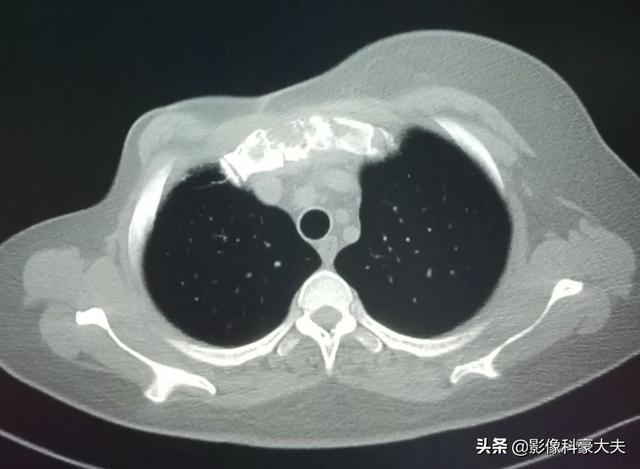

がんは体の様々な部位の骨に転移する可能性がありますが、最も一般的なのは一般的に中軸骨(すなわち背骨の胸椎と腰椎)、骨盤、肋骨、肩甲骨です。転移した骨のどの部分にも痛みが生じます。例えば、腰椎への転移は腰痛を引き起こし、肩甲骨への転移は肩の痛みを引き起こす。さらに、転移部の痛みで治療を受ける患者もいる。私の印象に残っているのは、40代の患者さんで、肩の痛みがあり、五十肩と思い、薬用オイルを揉んでも効果がなく、だんだん痛みがひどくなり、痛みに耐えかねて病院を受診したところ、肺がんの肩甲骨への転移で、肩甲骨が転移腫瘍で破壊されているという診察結果でした。肺がん(頭部を切り取ったもの)の左肩甲骨の転移で、骨は腫瘍によって破壊されている。

骨転移が骨、一般的には肋骨に発生した場合にも病的骨折が起こることがありますが、これは転移が骨の正常な構造を破壊するため、骨が弱くなり、外力が加わったときに骨折しやすくなるためです。骨転移の中には、骨の周囲に軟部組織の腫瘤として現れるものもありますが、体表には現れないため、発見するのは容易ではありません。病的骨折(下の矢印)

この患者さんは右乳がんの手術後、胸骨に転移があり、放射線治療でコントロールされています。がん治療は進歩しています、簡単に希望を捨てないでください。